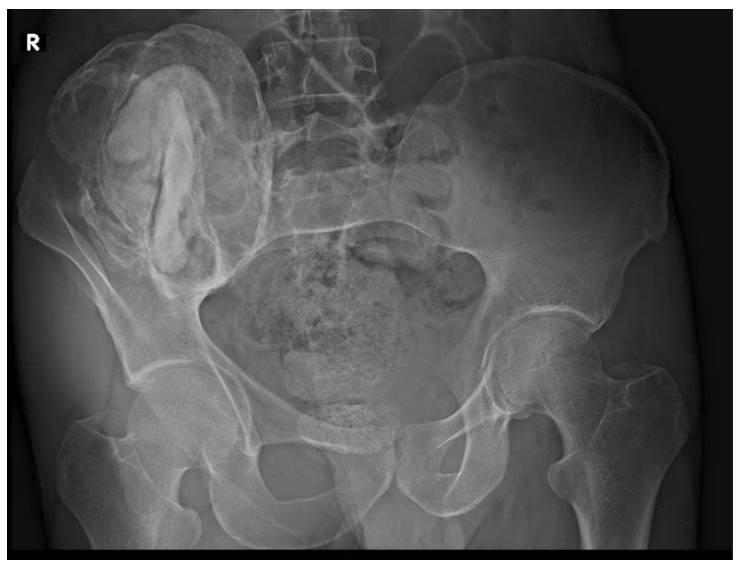

Ameliyat Öncesi: Röntgende sağ iliak kanatda düzensizlik, sement ve kitle lezyonu görülmekte